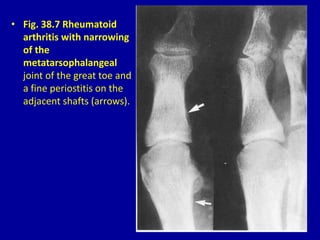

• Fig. 38.7 Rheumatoid

arthritis with narrowing

of the

metatarsophalangeal

joint of the great toe and

a fine periostitis on the

adjacent shafts (arrows).

• Fig. 38.7Rheumatoid arthritis with narrowing of the metatarsophalangeal joint of the great toe and a fine periostitis on the adjacent shafts (arrows).